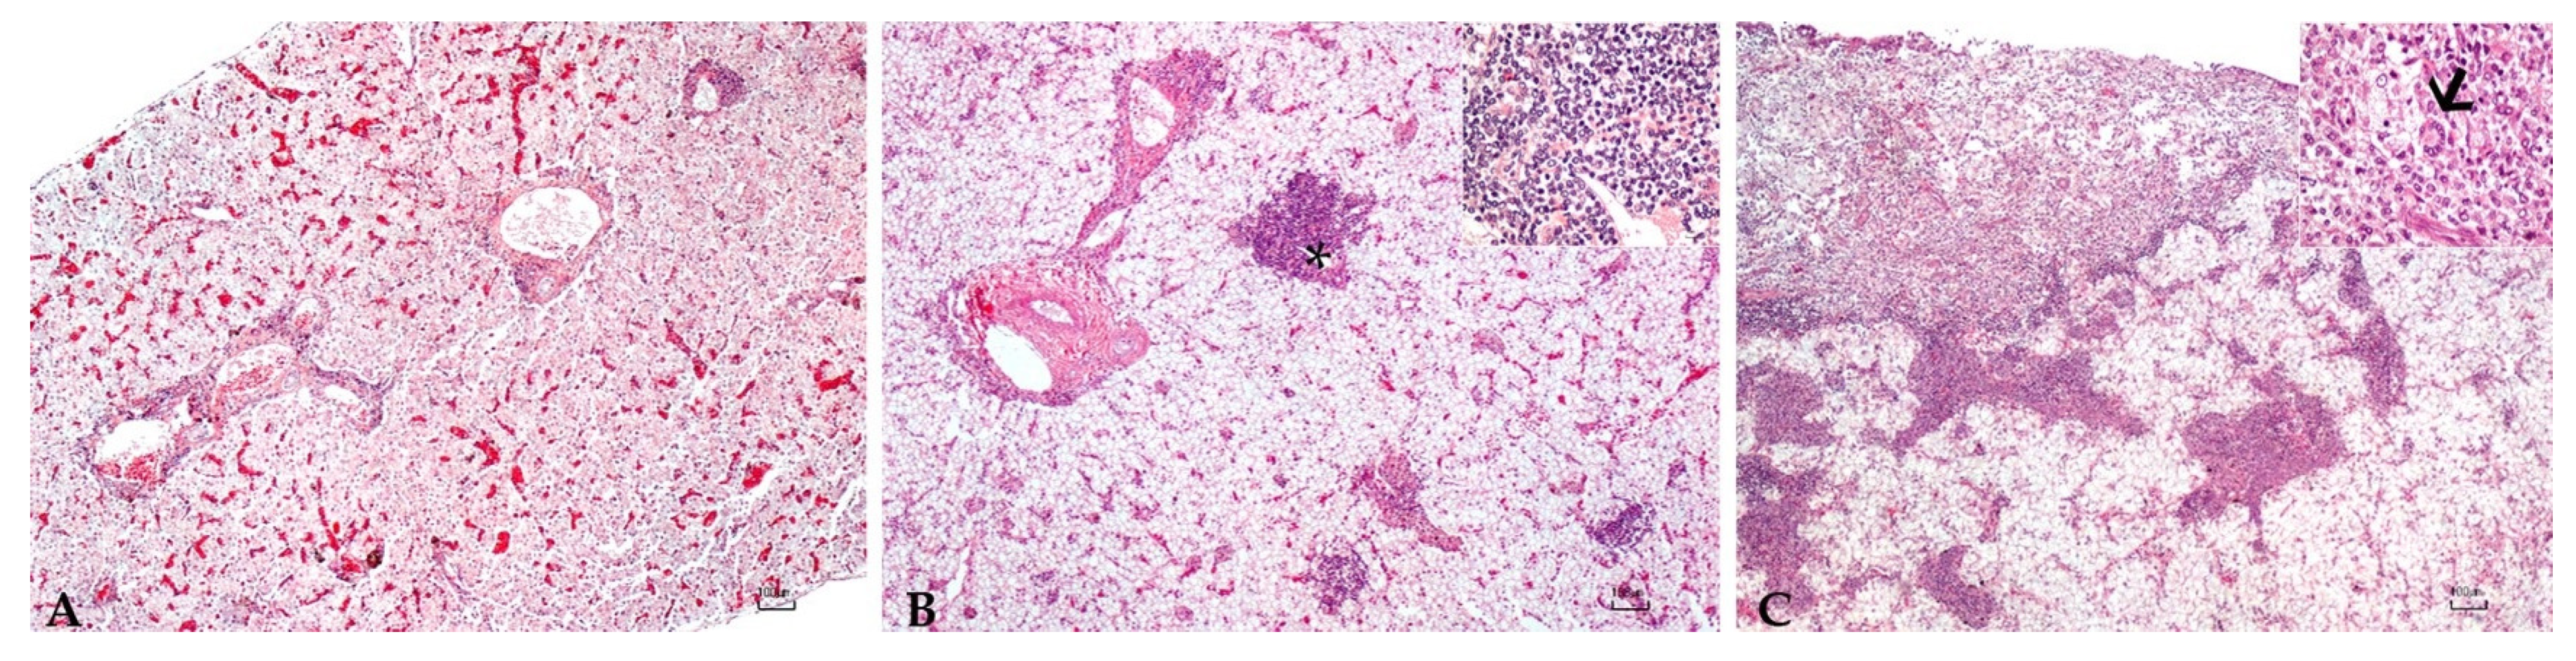

3.5. Histopathology

| ID | Liver | Spleen | Gut |

|---|---|---|---|

| 78697.1 | Severe inflammation | Severe inflammation | Severe inflammation |

| 78697.2 | Moderate inflammation | Mild inflammation/severe congestion | Mild inflammation |

| 78697.3 | Mild inflammation/severe congestion | Moderate inflammation | No lesion |

| 78697.4 | Moderate inflammation | No lesion | No lesion |